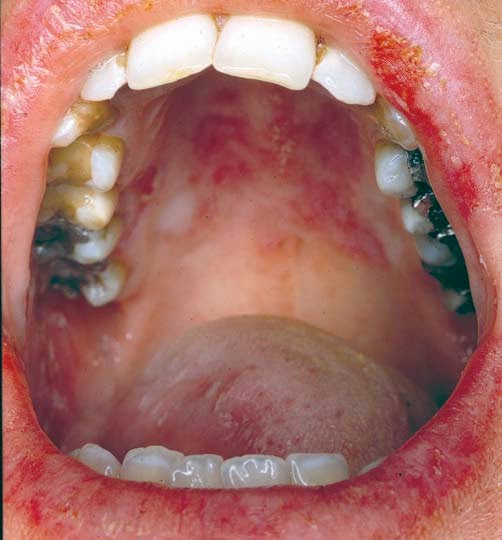

- Úlceras na boca (aftas).